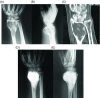

Giant cell tumor (GCT) of bone is a locally aggressive benign neoplasm that is associated with a large biological spectrum ranging from latent benign to highly recurrent and occasionally metastatic malignant bone tumor. It accounts for 4-10% of all bone tumors and typically affects the meta-epiphyseal region of long bones of young adults. The most common site involved is the distal femur, followed by the distal radius, sacrum, and proximal humerus. Clinical symptoms are nonspecific and may include local pain, swelling, and limited range of motion of the adjacent joint. Radiographs and contrast-enhanced magnetic resonance imaging (MRI) are the imaging modalities of choice for diagnosis. Surgical treatment with curettage is the optimal treatment for local tumor control. A favorable clinical outcome is expected when the tumor is excised to tumor-free margins, however, for periarticular lesions this is usually accompanied with a suboptimal functional outcome. Local adjuvants have been used for improved curettage, in addition to systematic agents such as denosumab, bisphosphonates, or interferon alpha. This article aims to discuss the clinicopathological features, diagnosis, and treatments for GCT of bone.